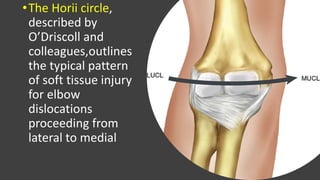

•The Horii circle,

described by

O’Driscoll and

colleagues,outlines

the typical pattern

of soft tissue injury

for elbow

dislocations

proceeding from

lateral to medial

•The Horii circle, describedby O’Driscoll and colleagues,outlines the typical pattern of soft tissue injury for elbow dislocations proceeding from lateral to medial

4. Soft TissueInjury • O’Driscoll and colleagues described the disruption of soft tissue structures from lateral to medial in elbow dislocations originating at the lateral ulnar collateral ligament (LUCL) and, in cases of high energy trauma, progressing to disruption of the medial ulnar collateral ligament (MUCL). • After bony anatomy is restored, attention should be turned to the soft tissue structures for reconstruction. The annular ligament and LUCL should be repaired, because rotatory instability ensues with any deficit in the lateral collateral ligament (LCL) complex